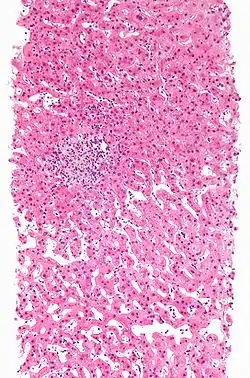

Hepatitis

Hierbij gaat de sterfte van de levercel (hepatocellulaire necrose) gepaard met een ontsteking. Er zijn drie soorten chemische hepatitis.

- Hepatitis A: 'virale' hepatitis. de meest voorkomende is de vorm die onder de microscoop sprekend op hepatitis door een virus lijkt. Oorzaken zijn onder andere halothaan, isoniazide of fenytoïne.

- Hepatitis B: bij focale of non-specifieke hepatitis vind je bij de ontstoken gebieden verspreide haardjes van celnecrose. Eén van de mogelijke oorzaken kan acetylsalicylzuur zijn.

- Hepatitis C: chronische hepatitis lijkt klinisch, serologisch, en onder de microscoop sterk op auto-immuunhepatitis. Oorzaken zijn onder andere: alfamethyldopa en diclofenac.